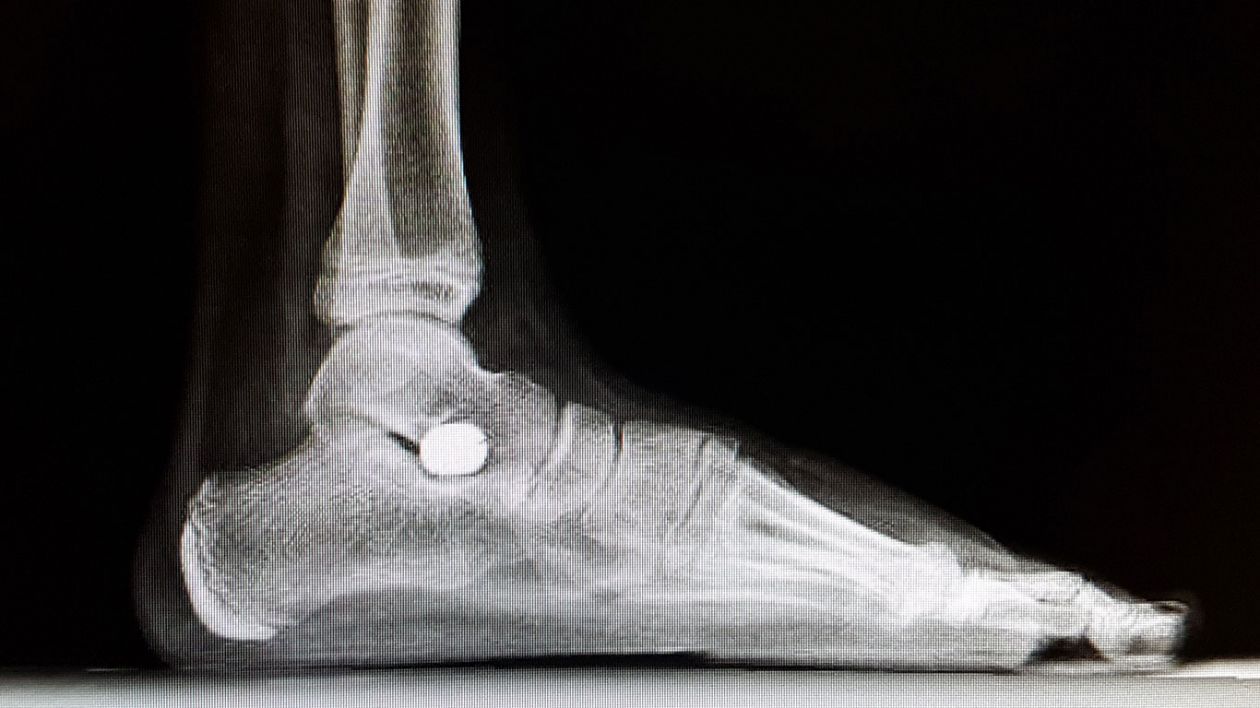

La epifisiolisis es un término médico que se refiere a una fractura del cartílago de crecimiento o fisis de un hueso largo. El cartílago de crecimiento, ubicado entre la epífisis y la metáfisis del hueso y constituido por células cartilaginosas que están estratificadas de manera muy precisa, responsables del crecimiento en longitud del hueso. Una vez finalizado el crecimiento, la zona se osifica desapareciendo el cartílago. Entre un 15% al 25% de las fracturas de la infancia afectan al cartílago fisario de crecimiento. La fractura puede ir recorriendo o cruzar dicha estructura, provocando como resultado la separación de una parte o la totalidad de la epífisis de la metáfisis.